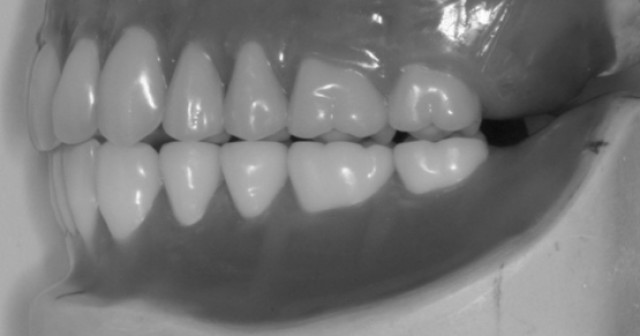

Using this tooth shade matching technique makes selecting a reference tooth shade easy, efficient, and predictable for restorative dentists chairside.